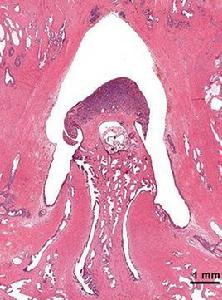

神經母細胞瘤是兒童中常見的實體瘤,它起源於神經脊,通常對它較難做出確切診斷。因為諸如橫紋肌肉瘤、Wilms腫瘤等同神經母細胞瘤一樣,有時也是由未分化的小燕麥細胞組成。近年來,研究者們套用NSE都可以做出鑑別診斷。神經母細胞瘤的NSE活性異常增高,而橫紋肌瘤和Wilms腫瘤的NSE活性卻仍然處在低水平值。此時,如有可能分析B亞基的烯醇化酶活性,就能發現橫紋肌肉瘤患者的酶活性水平均明顯地高於另外兩種腫瘤。